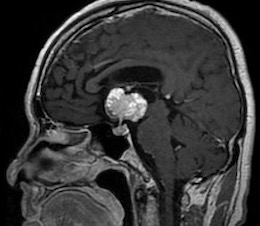

手術は通常通り行われ、顔面神経の麻痺を起こさずに摘出は終了し、うまくいったと考えていました。しかし術後より覚醒障害が続き、強い小脳腫脹を生じたため、術後脳室ドレナージ術、バルビタール麻酔療法、気管切開まで行い急性期を乗り切りました。術前より下肢静脈血栓症を合併していたことと、Petrosal veinが通常より広範囲の静脈環流を行っていたためと考えられます。現在、覚醒し、四肢が動くようになってきました。

手術は通常通り行われ、顔面神経の麻痺を起こさずに摘出は終了し、うまくいったと考えていました。しかし術後より覚醒障害が続き、強い小脳腫脹を生じたため、術後脳室ドレナージ術、バルビタール麻酔療法、気管切開まで行い急性期を乗り切りました。術前より下肢静脈血栓症を合併していたことと、Petrosal veinが通常より広範囲の静脈環流を行っていたためと考えられます。現在、覚醒し、四肢が動くようになってきました。